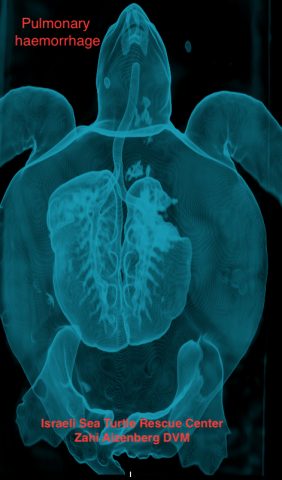

צבת הים משה, נמצאה כשהיא צפה בים מול מרינה הרצליה במרץ השנה והובאה למרכז ההצלה כשהיא תשושה מאד ומלאה בטפילים, מה שמצביע על כך כי היא צפה זמן רב מאד ללא יכולת לצלול ולאכול. היא טופלה באנטיביוטיקה ונוזלים ולאחר בדיקה מקיפה יותר הכוללת בדיקת CTבמרפאתו של הוטרינר ד"ר צחי אייזנברג התברר כי משה סובלת מכיס אוויר בריאה הימנית .

ד"ר צחי אייזנברג שאב מהריאה כ- 6 ליטר אוויר במסגרת הטיפול שניתן לה ולאחר חודשיים בבדיקה חוזרת הכוללת סריקת CT נמצא כי כיס האוויר נעלם כמעט לחלוטין. עם השלמת הטיפול בה ותקופה התאוששות והשגחה צמודה הוחלט במרכז הארצי להצלת צבי ים כי היא כשירה לחזור לים.